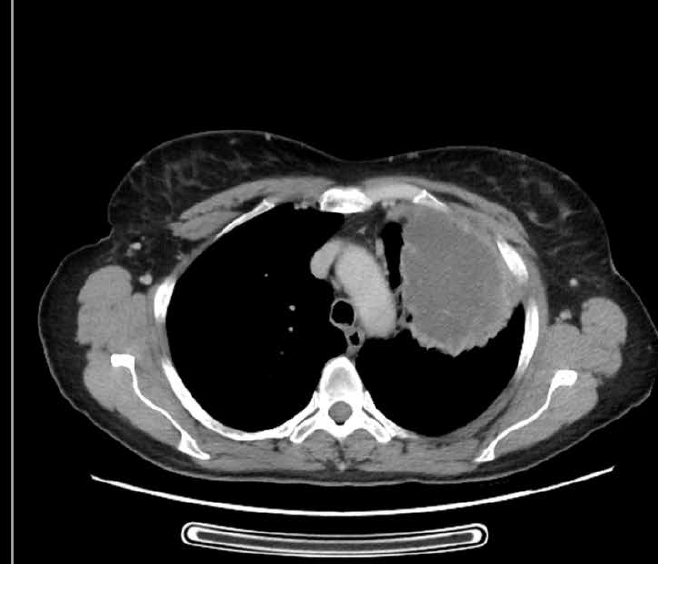

What is this?

Lung mets